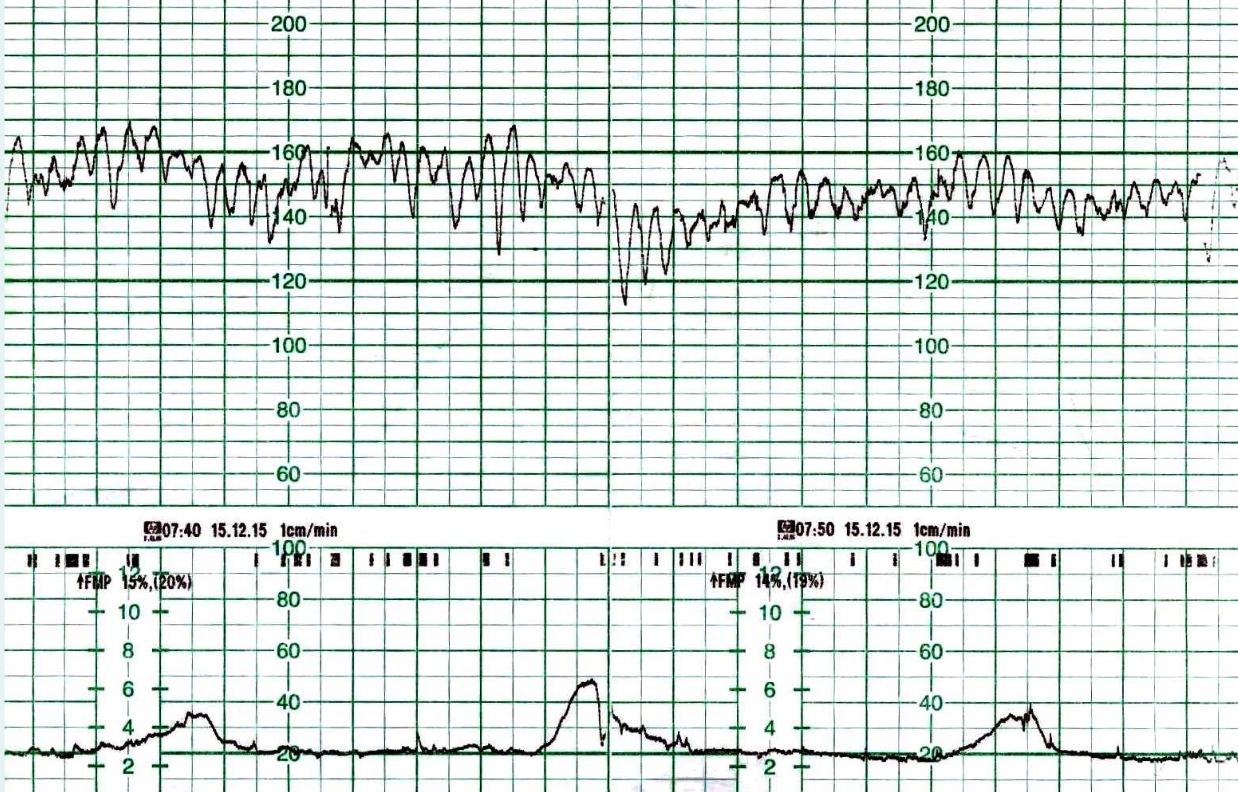

ABNORMAL CTGs:

Sinusoidal - what does this mean?

A

Sinusoidal usually refelects anaemia (severe), No variaility, complete loss of autonomic control